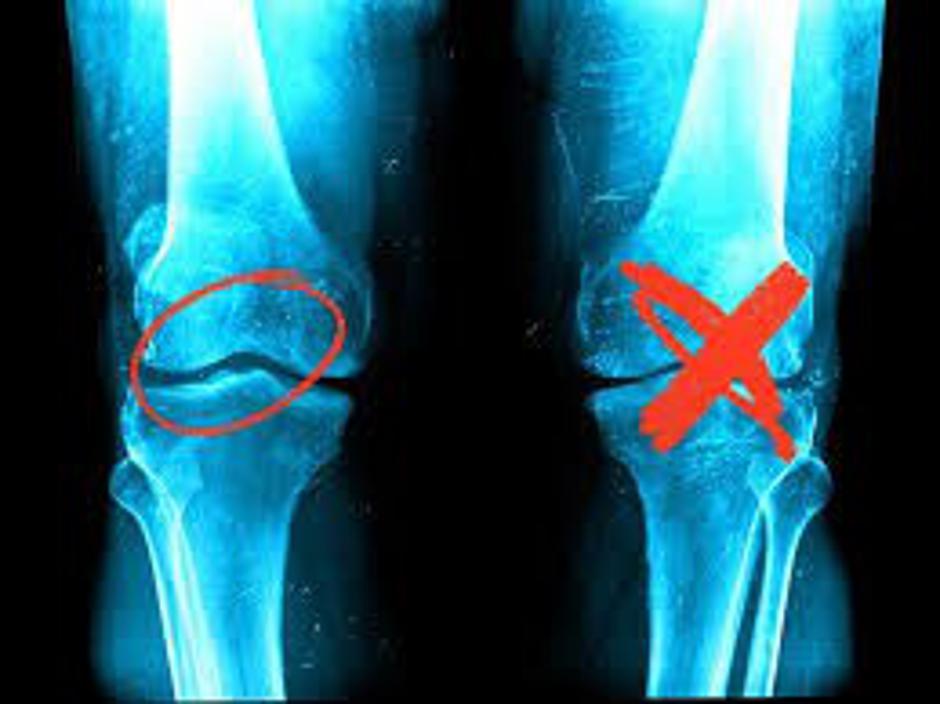

Ako imate slomljene kosti, pokidane tetive ili uvrnute zglobne čahure - potrebna vam je hitna kirurška intervencija. No, ako se borite s bolovima uzrokovanim artrozom, bolestima zglobova, mišićima ili leđima, nubi terapija magnetskim kamenjem je za vas. Njihovi su učinci jednostavno nevjerojatni.